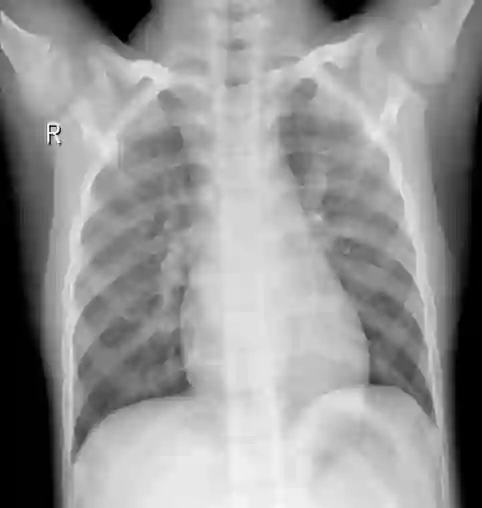

Pneumonia remains a leading cause of morbidity and mortality worldwide. Chest X-ray (CXR) imaging is a fundamental diagnostic tool, but traditional analysis relies on time-intensive expert evaluation. Recently, deep learning has shown immense potential for automating pneumonia detection from CXRs. This paper explores applying neural networks to improve CXR-based pneumonia diagnosis. We developed a novel model fusing Convolution Neural networks (CNN) and Vision Transformer networks via model-level ensembling. Our fusion architecture combines a ResNet34 variant and a Multi-Axis Vision Transformer small model. Both base models are initialized with ImageNet pre-trained weights. The output layers are removed, and features are combined using a flattening layer before final classification. Experiments used the Kaggle pediatric pneumonia dataset containing 1,341 normal and 3,875 pneumonia CXR images. We compared our model against standalone ResNet34, Vision Transformer, and Swin Transformer Tiny baseline models using identical training procedures. Extensive data augmentation, Adam optimization, learning rate warmup, and decay were employed. The fusion model achieved a state-of-the-art accuracy of 94.87%, surpassing the baselines. We also attained excellent sensitivity, specificity, kappa score, and positive predictive value. Confusion matrix analysis confirms fewer misclassifications. The ResNet34 and Vision Transformer combination enables jointly learning robust features from CNNs and Transformer paradigms. This model-level ensemble technique effectively integrates their complementary strengths for enhanced pneumonia classification.